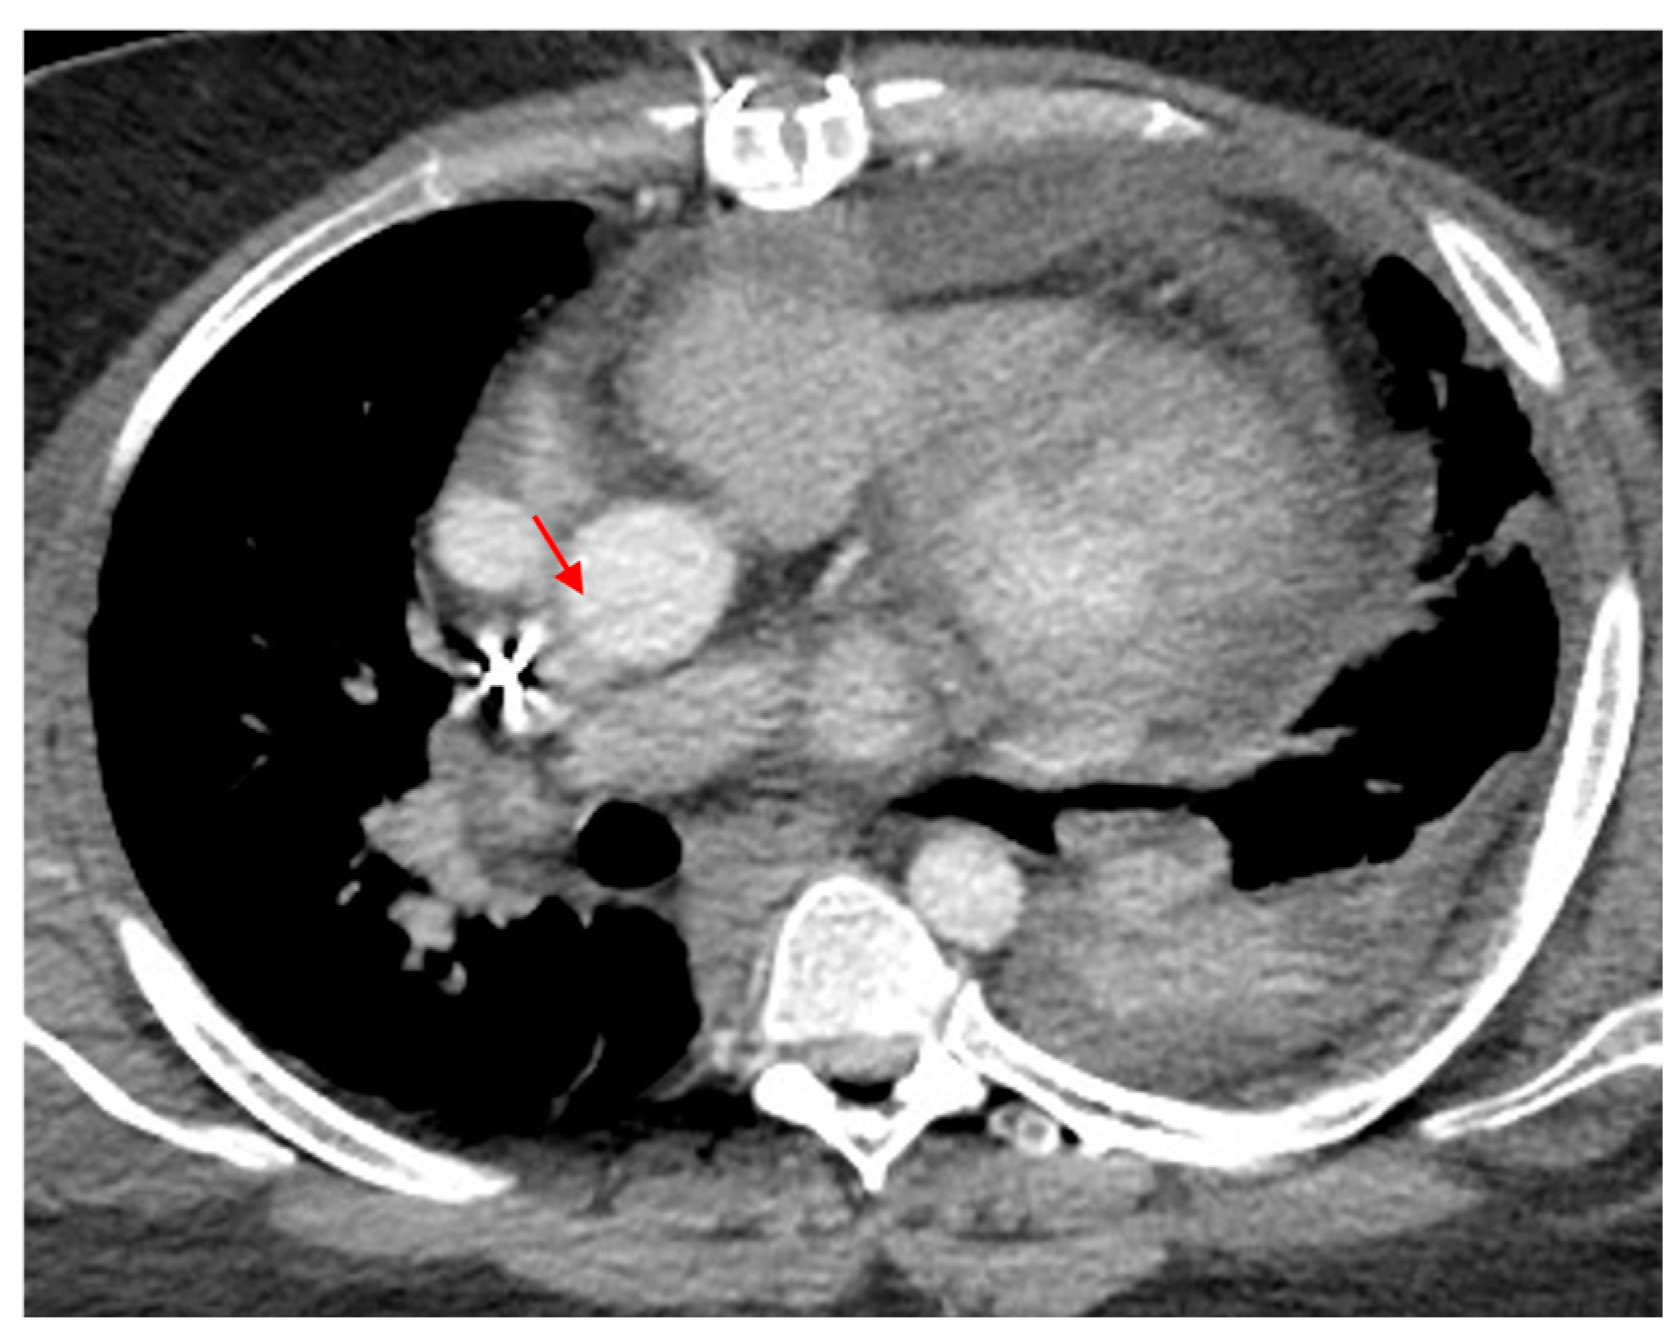

3.1.2. Indirect Signs of Aortic Injury